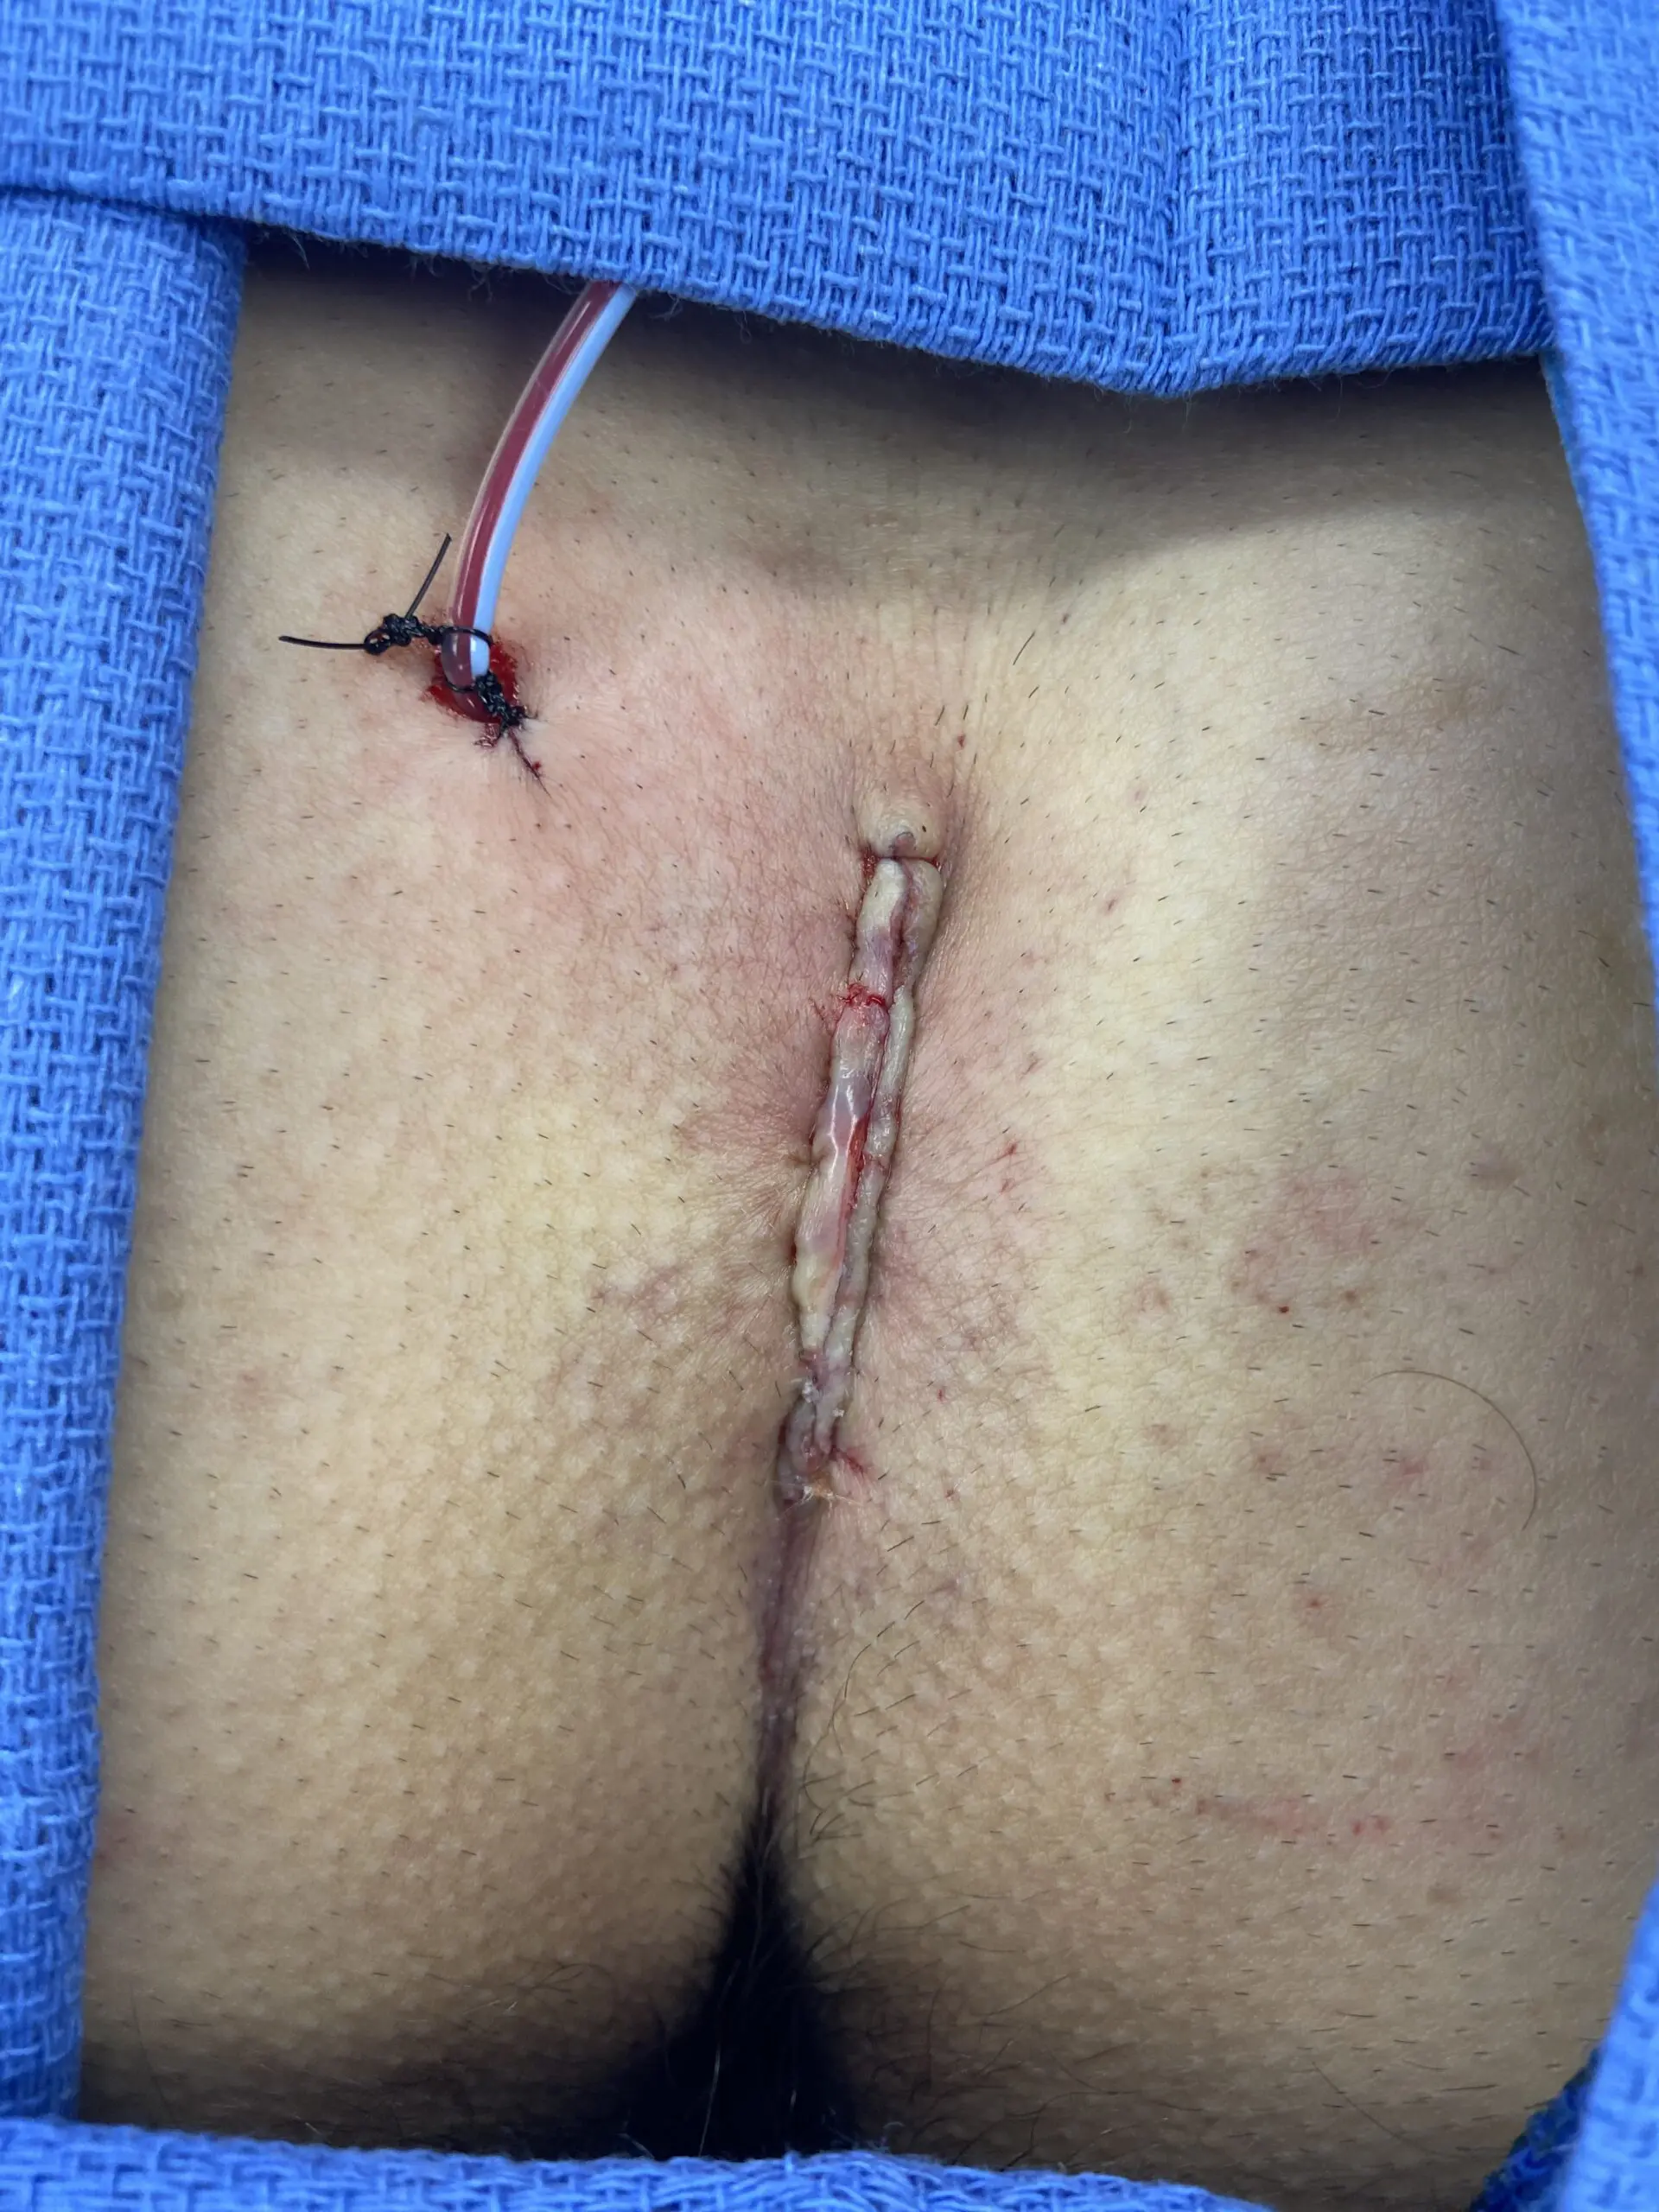

Primary Closure

Kerecis can be applied under the suture line to support reinforcement and reduce the risk of dehiscence. In the case series below, five patients undergoing pilonidal cyst excision fully healed with Kerecis placed as an underlay to the skin closure.

Patient Presentation

5 patients undergoing pilonidal cyst excision were included in this clinical series

All patients were male and the average age was 26 (range 22-29).

All patients received 2 grams of cephazolin preoperativel

Surgical Intervention and Kerecis Graft Application

SurgiBind reconstituted in a vancomycin/saline solution was placed as an underlay to the skin closure.

Clinical Outcome

All wounds healed uneventfully, and all sutures were removed at Day 10.

No wounds demonstrated any signs of infection or wound dehiscence.

This small pilot study suggests the possible role of full thickness fish skin underlay in preventing wound dehiscence in patients undergoing primary closure after pilonidal cyst excision